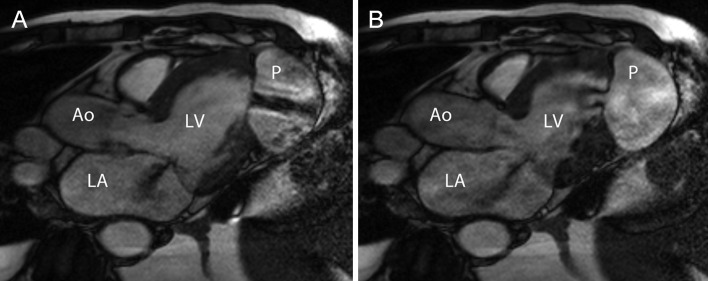

A cardiac MRI (Fig. 1 and Supplementary Video 1) and a transthoracic echocardiography (Supplementary Video 2) demonstrated a left ventricular pseudoaneurysm and showed blood passing in and out through a small left ventricular apical inferolateral wall defect.

Figure 1:

Cardiac MRI clearly shows a jet (black) from blood passing into (A) and back (B) through a small left ventricular inferior wall defect. Three-chamber view, early (A) and late (B) systole. Ao = aorta, LA = left atrium, LV = left ventricle, P = pseudoaneurysm.